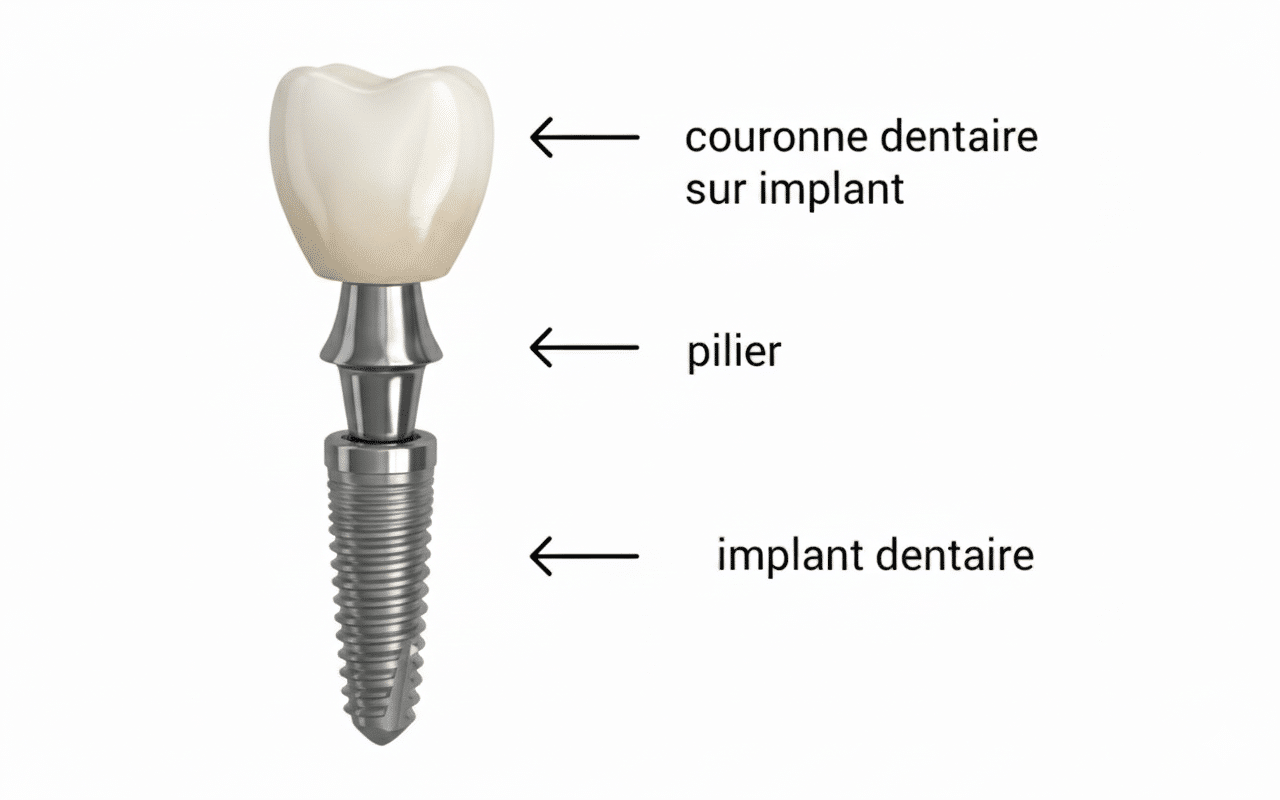

Pack Implant Dentaire

Tout inclus – Qualité garantie